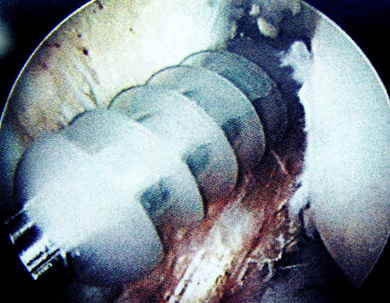

關節(jié)鏡下見重建的前交叉韌帶